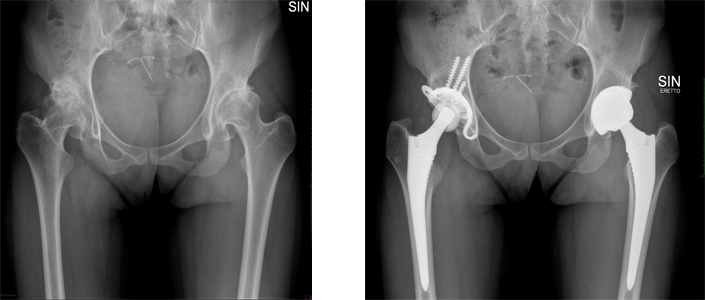

Artroplastica dell'anca

In seguito a fratture, a deformità diverse o ad altre malattie, l’articolazione dell’anca può essere distrutta in un modo irreversibile. Questa evoluzione dura spesso per un periodo lungo.

Nel corso del ventesimo secolo, e soprattutto dopo gli anni ’60, sono state sviluppate protesi che simulano la funzione dell’anca.

Benché queste protesi diano spesso un risultato funzionale eccellente dopo l’intervento, la sostituzione protetica dell’anca è conosciuta per uno scollamento progressivo degli impianti e altri problemi a lungo termine.